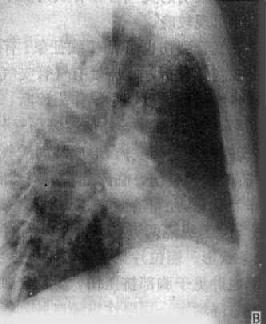

左肺外围型肺癌

图3-1-30 左肺外围型肺癌

体层摄影,左肺野可见圆形病灶, 边缘毛糙,有毛刺